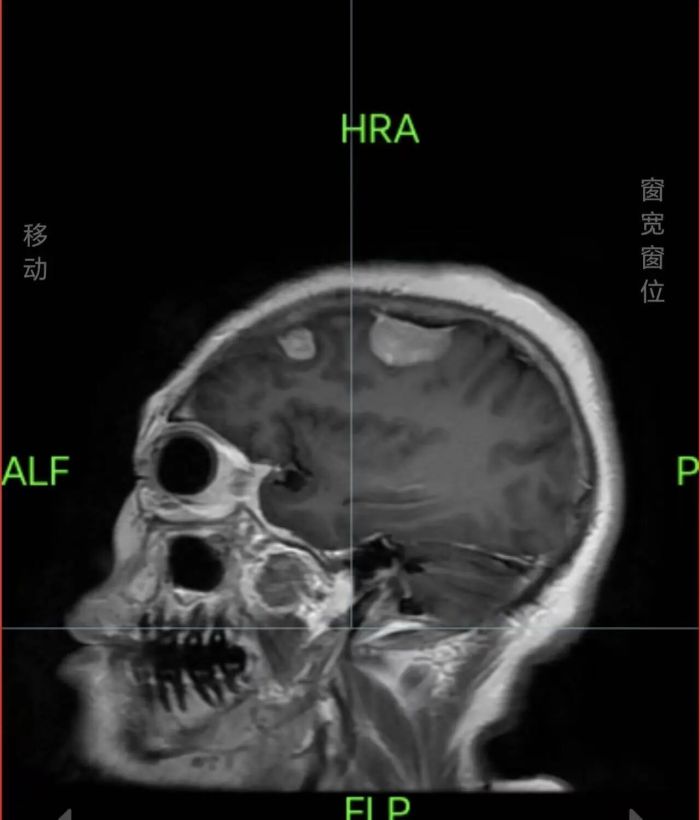

入院后,医生结合王女士的症状,立即为其安排了头颅检查,检查结果令人揪心——右侧顶部存在占位性病变,确诊为脑膜瘤,且不止1颗,而是4颗。这一结果让王女士及家属陷入恐慌,担忧手术风险高、难以彻底切除。

针对患者病情,神经外科团队立即组织病例讨论,结合患者年龄、身体状况及肿瘤的位置、大小,综合评估后,制定了个性化手术方案,决定为其实施开颅显微镜下神经内镜下右侧顶部占位性病变切除术+颅内压探头植入术+骨微动力系统开颅术。

脑部手术被誉为“在毫厘之间刀尖起舞”,更何况是同时切除4颗肿瘤,对手术精度和医生技术有着极高要求。手术当天,神经外科副主任廖鑫、主治医师刘永茂及其医护团队默契配合,借助显微镜与神经内镜的协同优势,精准定位肿瘤位置,小心翼翼地分离肿瘤与周围脑组织、神经血管,避开重要功能区,逐一将4颗肿瘤完整摘除。整个手术过程顺利,出血少、创伤控制精准。经病理学检查,四颗肿瘤均为良性肿瘤,患者预后较好。